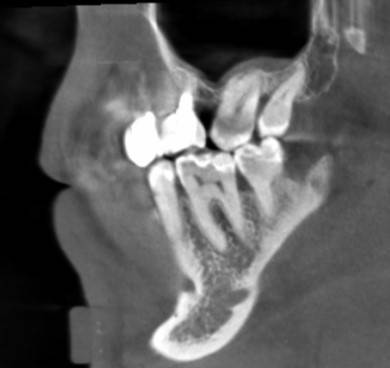

Александр9 Опубликовано 24 ноября, 2021 Автор Поделиться Опубликовано 24 ноября, 2021 спасибо за ответы! Впервые наблюдал за лечением своего зуба на экране. С микроскопом оказалось действительно лучше, т.к. зуб достаточно глубоко был поражен и приходилось тщательно его "вычищать" изнутри. Правда в стенке все же образовалась дырка и пришлось ее заделывать "заплаткой". На снимке видно темные области под временной пломбой. Это не помешает проходить с ней 4 месяца до установки коронки? 1 Ссылка на комментарий

St. Опубликовано 26 ноября, 2021 Поделиться Опубликовано 26 ноября, 2021 По снимку все красиво! Под такой временной пломбой может быть неконтрастный материал или "ваточка". Тем не менее долго ходить с временной пломбой не стоит и чем быстрее Вы попадете на восстановление и коронку тем лучше (меньше риск что отколите остатки стенок и повторного попадения микробов). Кстати, если вдруг временная выпадет, обязательно показаться доктору и вернуть ее на место. без временной ходить категорически нельзя. 1 1 Ссылка на комментарий